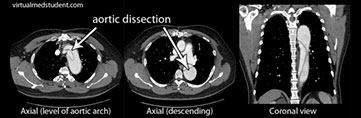

Διαχωρισμός Αορτής

Εικόνα Διαχωρισμού

Η παθογένεια της θωρακικής αορτής είναι πολύπλοκη και πιθανώς περιλαμβάνει μια φλεγμονώδη διεργασία, που προκαλεί νέκρωση των κυττάρων στον μέσο χιτώνα του τοιχώματος της αορτής. Μόλις η διάμετρος της αορτής φθάσει σε μια κρίσιμη διάμετρο (περίπου >5,5cm στην ανιούσα αορτή και 7cm στην κατιούσα αορτή), τότε το τοίχωμα της αορτής χάνει την ελαστικότητα του έτσι ώστε μια αύξηση στην πίεση του αίματος, περίπου 200mm Hg (όπως μπορεί να συμβεί κατά τη διάρκεια στρες ή άσκησης) μπορεί να ξεπεράσει την αντοχή του αρτηριακού τοιχώματος και να προκληθεί ρήξη ή διαχωρισμός. Ο διαχωρισμός της αορτής ξεκινά με ένα σχίσιμο στον έσω χιτώνα της αορτής. Το σχίσιμο αυτό επιτρέπει μια ποσότητα αίματος υπό πίεση να περάσει μέσα στους χιτώνες του αορτικού τοιχώματος, σχηματίζοντας ένα αιμάτωμα το οποίο διαχωρίζει το έσω από τον έξω χιτώνα και δημιουργεί ένα ψευδή αυλό. Ο ψευδής αυλός επεκτείνεται σε μία απόσταση που ποικίλει προς κάθε κατεύθυνση.

FL: false lumen ψευδής αυλός

ΤL: true lumen αληθής αυλός